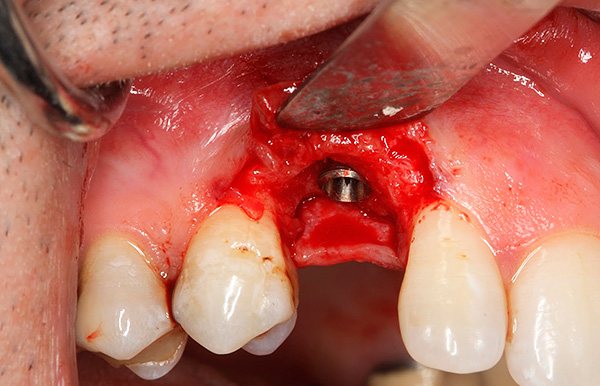

На фотографиях ниже показаны удаленные импланты:

После удаления подвижного импланта проводят процедуру комплексной подготовки лунки к следующей имплантации, которую могут осуществить уже через 1-2 месяца. Например, при значительной убыли костной ткани или близости к гайморовой пазухе может потребоваться наращивание кости челюсти под зубной имплант (операция синус-лифтинга).